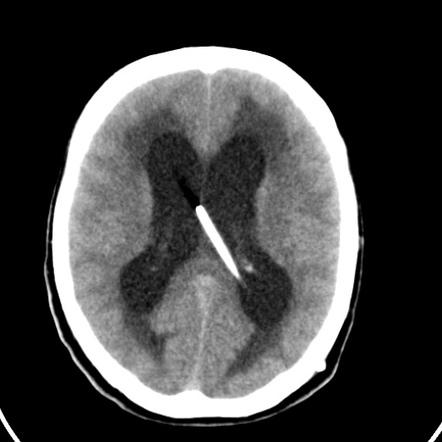

The Hydrocephalus Shunts market is witnessing significant advancements fueled by technological innovations and increasing demand for effective cerebrospinal fluid management solutions. Industry dynamics are evolving, propelled by rising incidence rates of hydrocephalus globally and improvements in shunt design that enhance patient outcomes. Market insights reveal an upward trajectory in market...